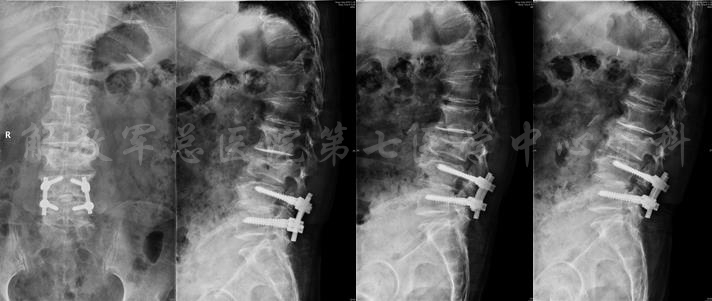

为患者实施腰4-5椎间融合手术后,效果良好。术后三年,患者再次入院。

诊断为腰椎管狭窄症;邻近节段退变;胸腰段后凸畸形;肌少症。并定制相关治疗措施,最后患者康复出院。